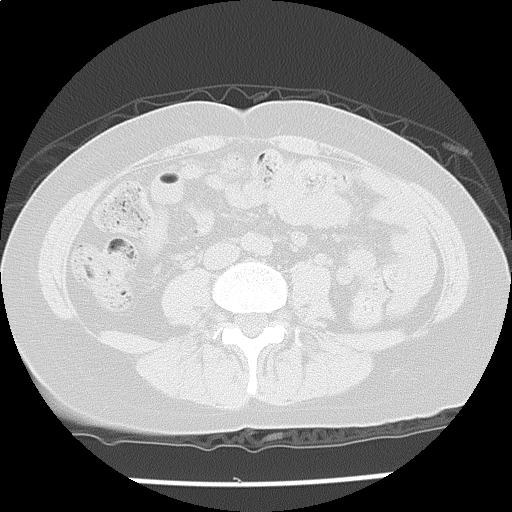

健診で腹部CTで両下野に結節指摘あり

年齢: 51歳

性別: 女性

検査部位: 胸腹部

検査種別: CT

CTスライス画像

CTスライス1